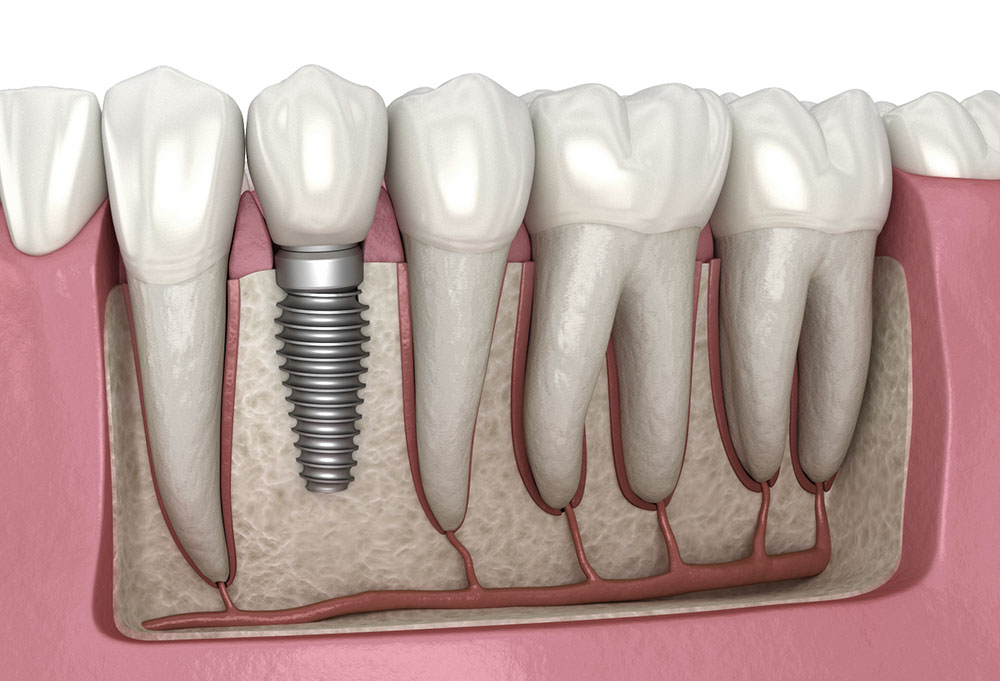

Η τοποθέτηση οδοντικών εμφυτευμάτων αποτελεί την πιο σύγχρονη και αξιόπιστη λύση για την αντικατάσταση ενός ή περισσότερων δοντιών που έχουν χαθεί. Τα εμφυτεύματα προσφέρουν:

Διάγνωση και σχεδιασμός – ψηφιακές ακτινογραφίες και 3D απεικόνιση για τον ακριβή προγραμματισμό.

Τοποθέτηση εμφυτεύματος – χειρουργική διαδικασία με τοπική αναισθησία, πλήρως ανώδυνη.

Περίοδος οστεοενσωμάτωσης – το εμφύτευμα ενσωματώνεται στο οστό, παρέχοντας σταθερή βάση για τη μελλοντική αποκατάσταση.

Αποκατάσταση με στεφάνη ή γέφυρα – ολοκληρώνεται η αισθητική και λειτουργική αποκατάσταση.